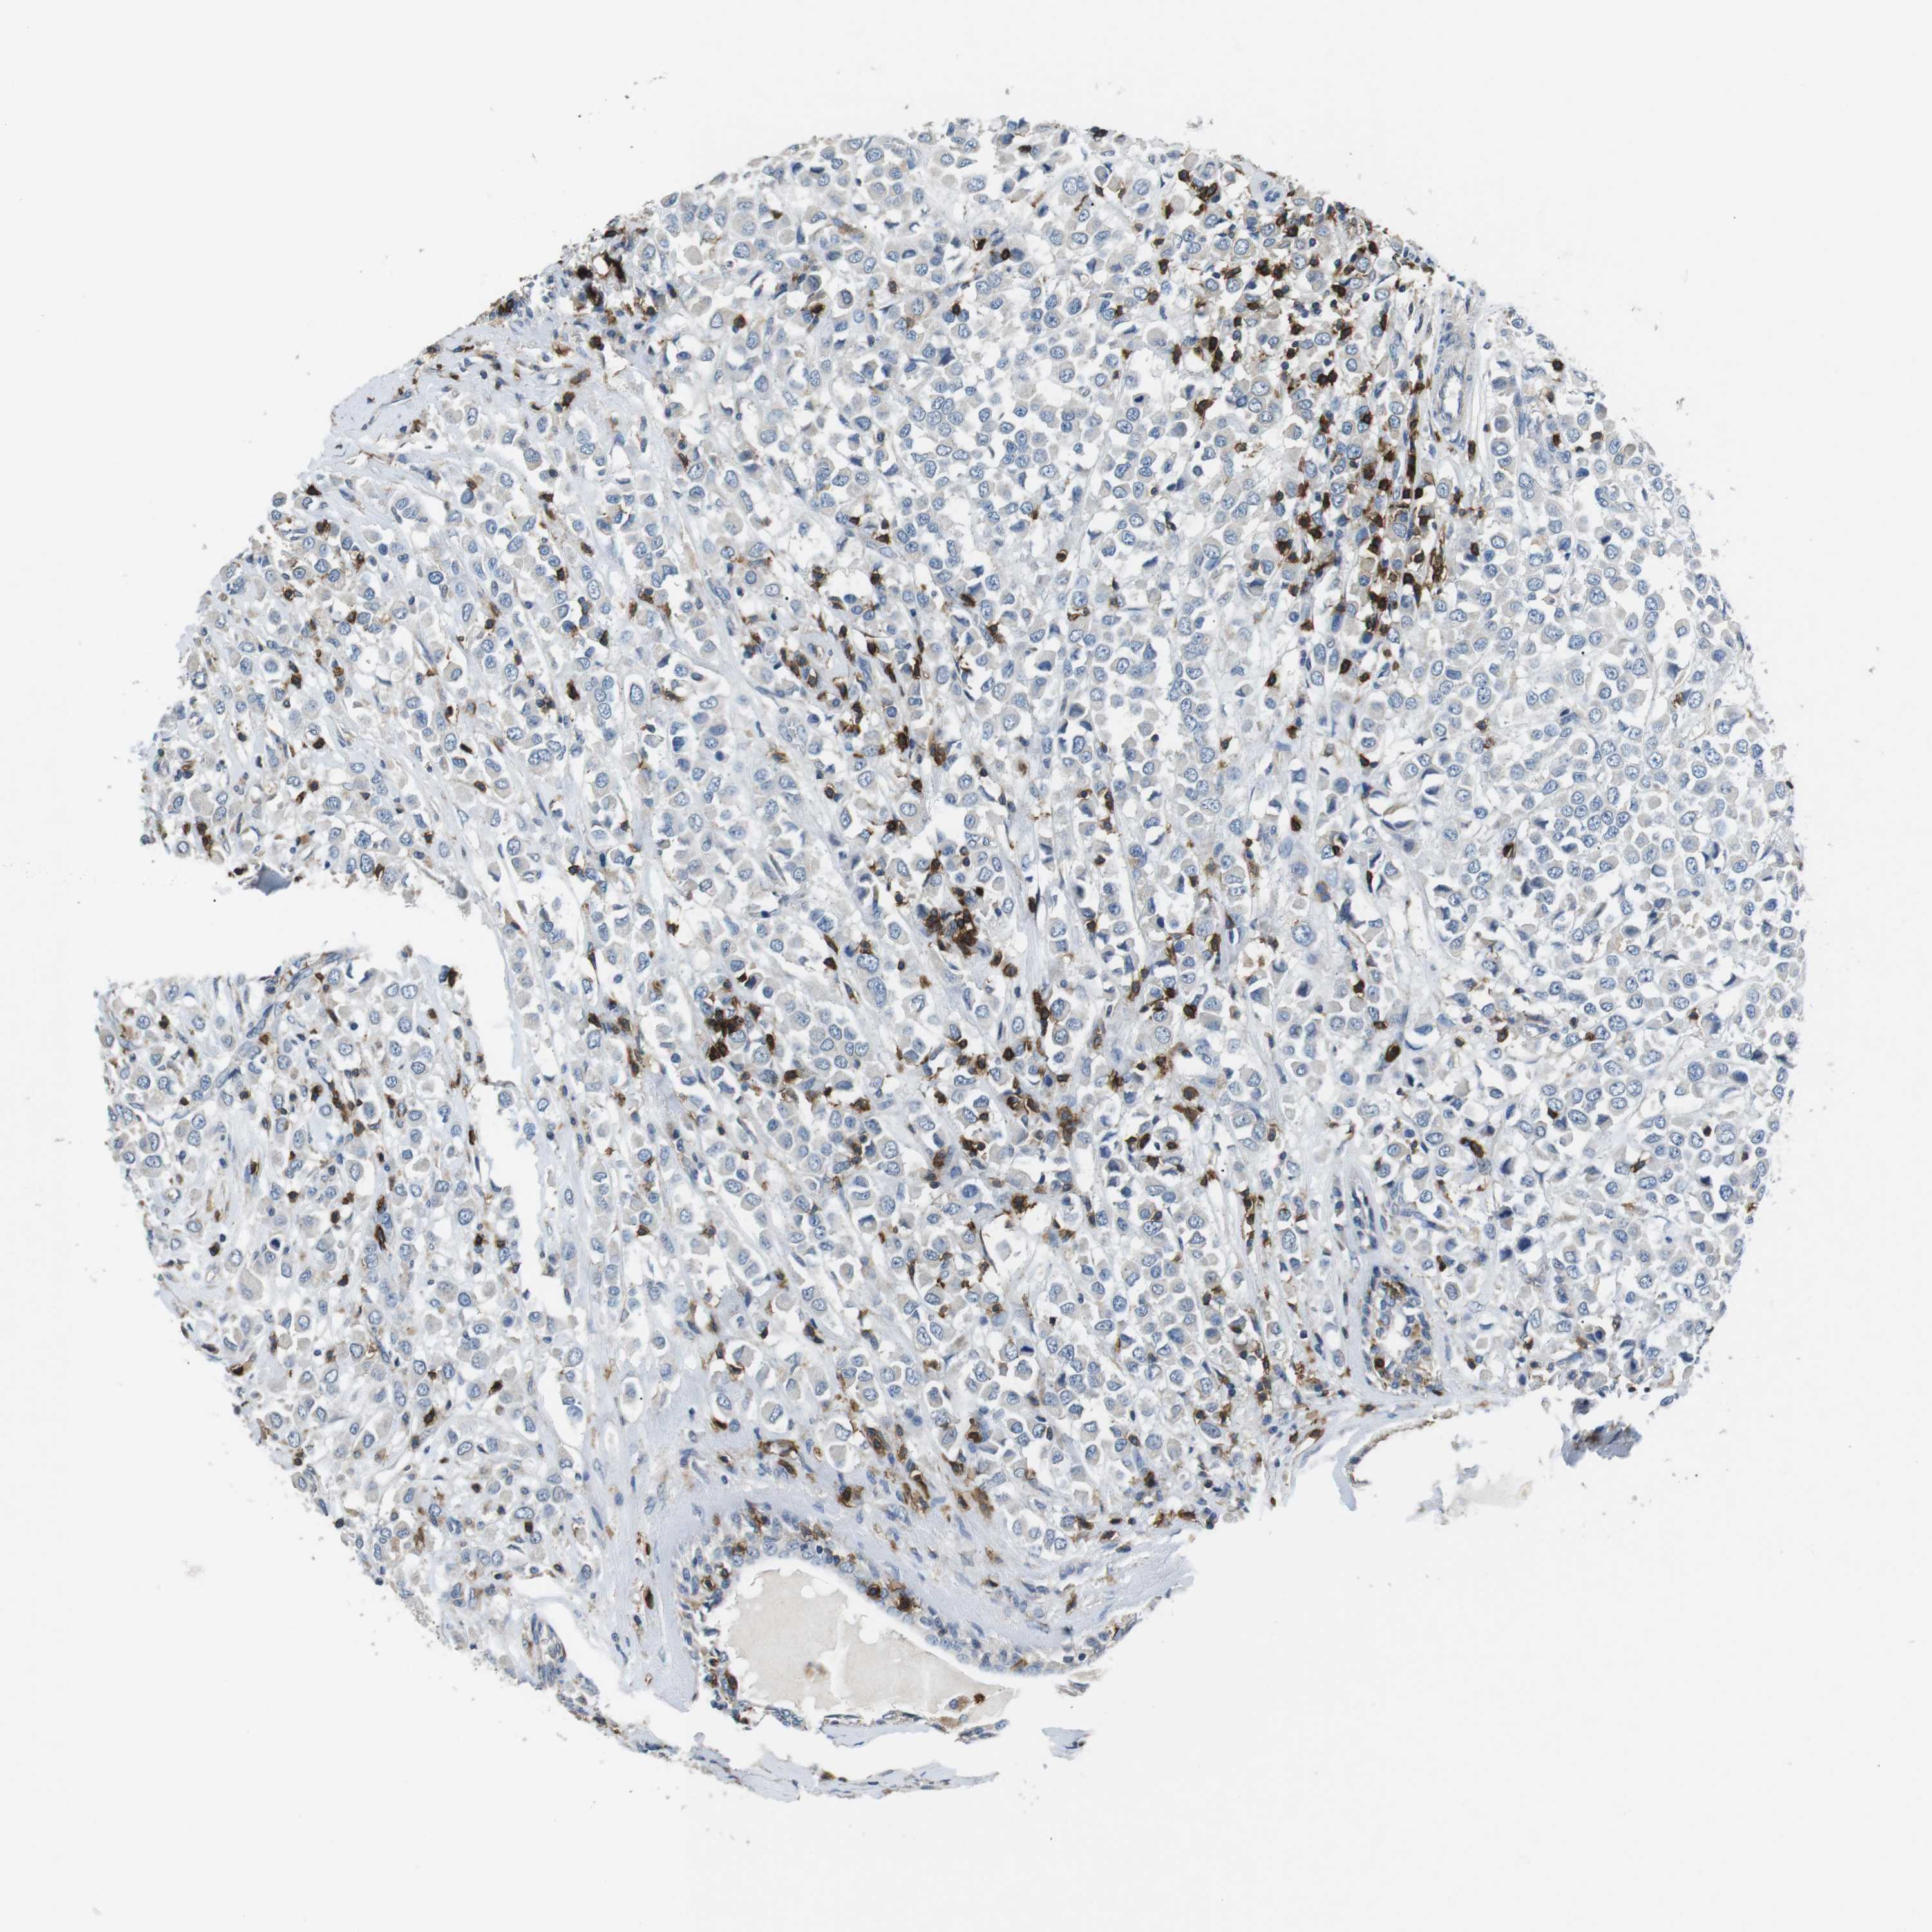

CANCER BREAST CANCER Show tissue menu

BRCA TCGA BRCA VALIDATION PROTEIN EXPRESSION

Breast cancer

Human cancer

CD6 is potential prognostic, high expression is favorable in Breast Invasive Carcinoma (TCGA)